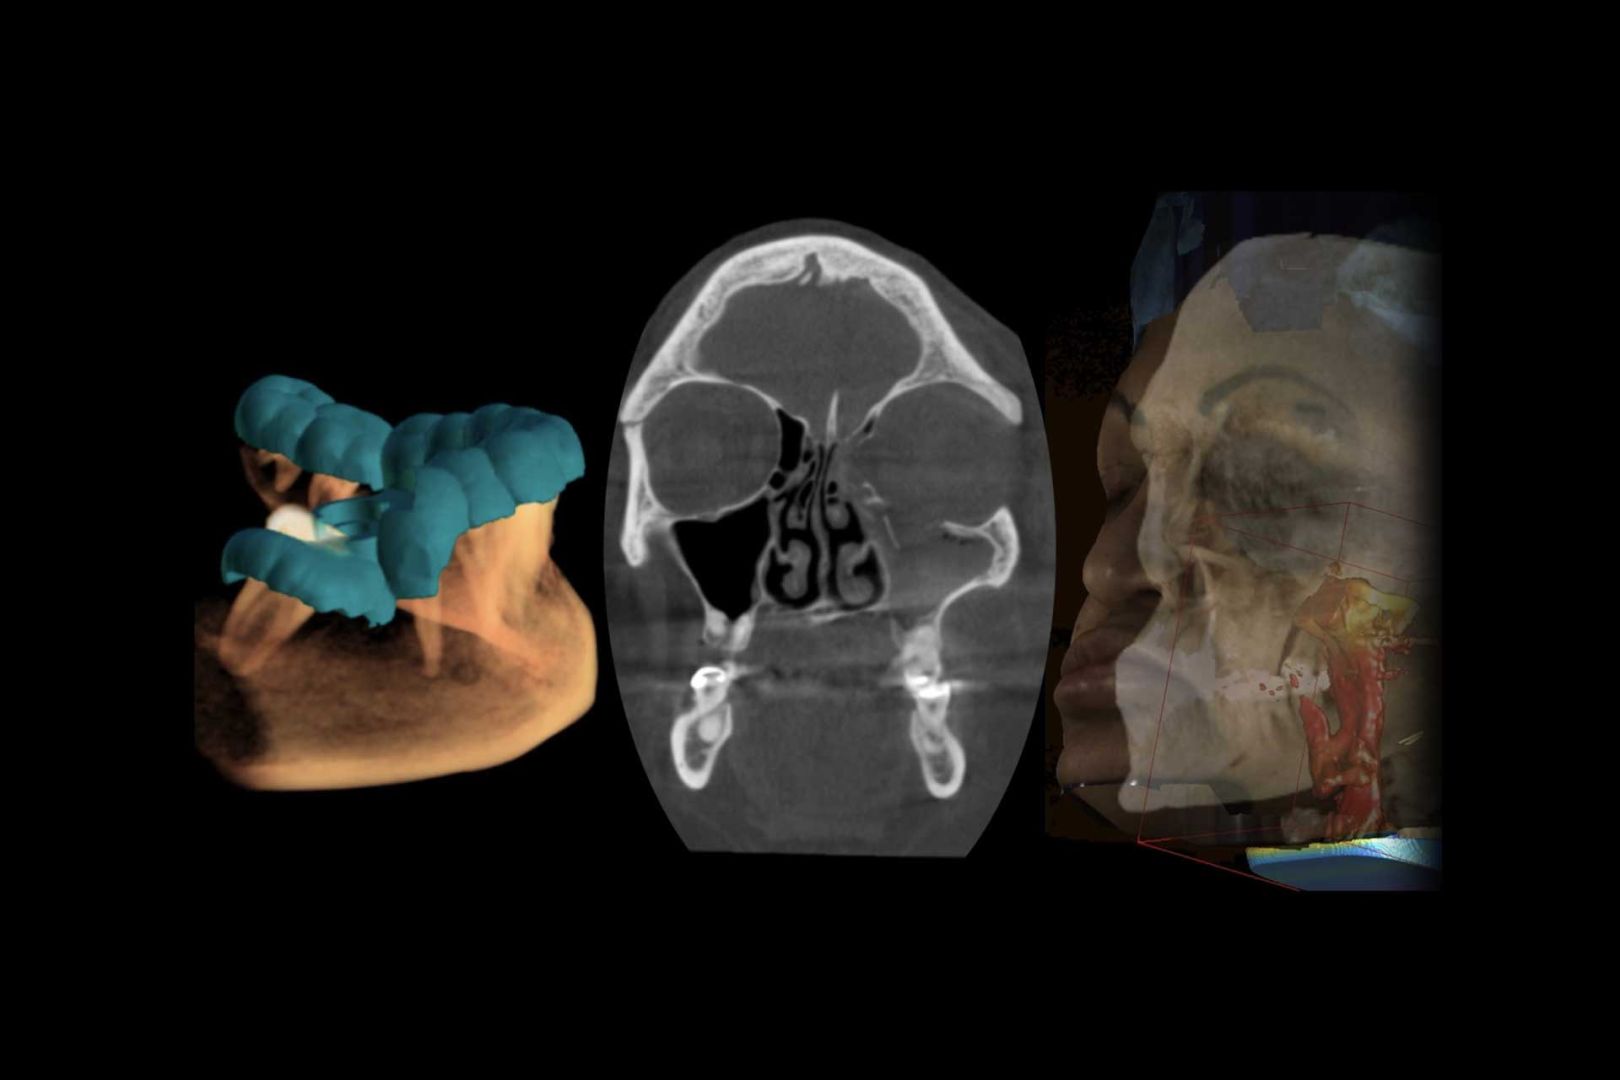

Especialízate en Imagenología Oral y Maxilofacial en la Universidad Finis Terrae, adquiriendo formación avanzada en Tomografía Cone Beam y tecnologías de vanguardia para la correcta adquisición, procesamiento e interpretación de imágenes, con un enfoque preciso y actualizado para la práctica odontológica.

Una de las áreas con mayor avance tecnológico en la última década en el área odontológica moderna a nivel nacional e internacional ha sido la Imagenología Oral y Máxilofacial, en donde se destaca la Tomografía de alta resolución Cone Beam. La formación especializada para obtener el Titulo de Especialista en Imagenología Oral y Maxilofacial, es un programa exclusivo entregado por la Universidad Finis Terrae, que permite a los profesionales de la odontología adquirir conocimientos de vanguardia para una adecuada aplicación, procesamiento e interpretación de las imágenes.

Incorporar competencias necesarias y capacitar a dentistas profesionales en el área de imagenología oral y máxilofacial con habilidades para interpretar, realizar diagnosticos y planificar tratamientos con mayor precisión.

El especialista en Imagenología Oral y Maxilofacial, formado en la Facultad de Odontología de la Universidad Finis Terrae, es un profesional con alto sentido de responsabilidad, honestidad, empatía y conciencia humanitaria, con firmes principios bioéticos, en beneficio de sus pacientes, apoyado en sólidos fundamentos científico-tecnológicos, especializado para realizar, indicar e interpretar correctamente exámenes imagenológicos por su sólida formación en anatomía y patología, con énfasis en las de mayor prevalencia del Área Oral y Máxilo Facial, respetando el cumplimento de las normas de bioseguridad y radio protección tanto para sí mismo como para los pacientes y personal de apoyo. Se relaciona y dialoga con las distintas especialidades de la odontología en donde es identificado como un referente en la indicación e interpretación de exámenes imagenológicos, demostrando ser un apoyo en el diagnóstico, planificación, tratamiento y control de éstos y en los proyectos de investigación clínica aplicada.